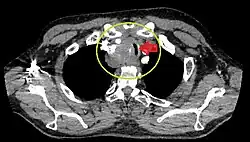

- Goitre comprimant la trachée cervicale.

Rétrécissement trachéal (flèche rouge). Tomodensitométrie (coupe transversale).

Même tumeur (coupe sagittale).